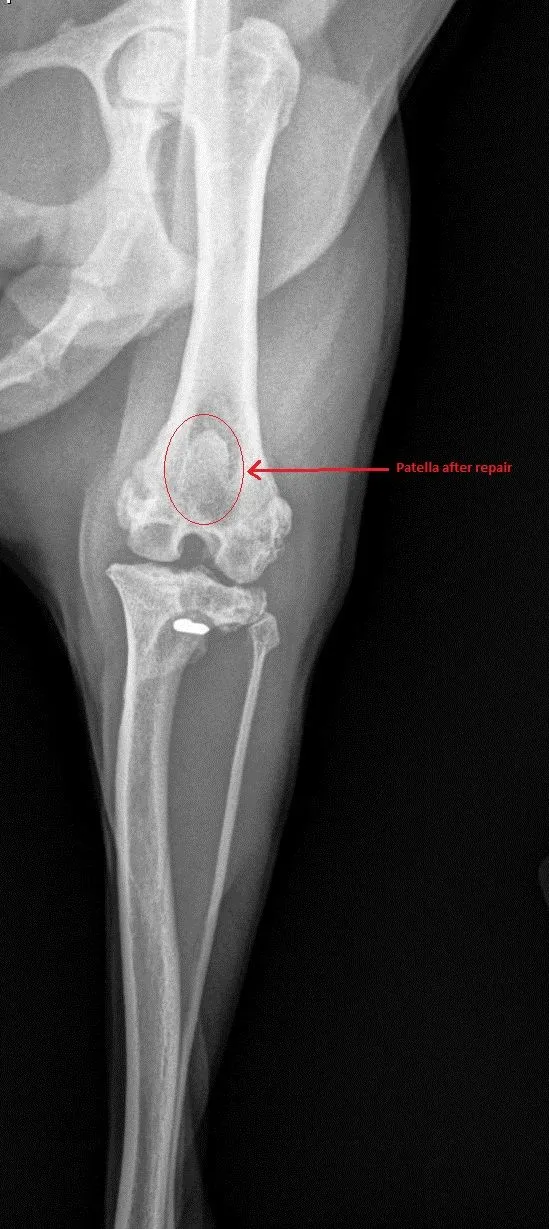

Patellar Luxation aka Luxating Knee caps most commonly seen in Toy breeds where knee cap is most commonly luxation to medial (inner side of knee joint) side resulting bowing of rear limb/limbs ,unstable knee prone to ACL inury and Chronic Arthritis. Surgical correction usually help to stabilize knee, reduce pain and slow down arthritis progression.